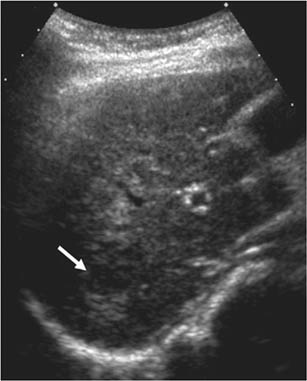

Percutaneous ethanol injection

Percutaneous ethanol injection (PEI) involves the imaging guided injection of ethanol into the tumor to induce coagulation necrosis (Figure 8) (66, 72). The non-subcapsular, non-perivascular nodules <2 cm are ideal for PEI because of its limited capacity to penetrate the tumor beyond its pseudo-capsule or fibrotic septa (60, 72). Although it is a cost-effective form of therapy, the recurrence tumor rate is higher when compared to other locoregional therapies, thus PEI has fallen into disfavor as the first line therapy for small HCC lesions. PEI has a recurrence-free survival rate of 77% at one year as compared to 86% in patients treated with radiofrequency ablation (RFA) (64). Its side effects include post procedural pain, and it requires several sessions to yield complete treatment (66).

Fig 8

Figure 8. Ultrasound-guided percutaneous alcohol injection of hepatocellular carcinoma. A and B. Under image-guidance by US, administration of ethanol (97%) is performed into the tumor. C. Noting an enlarging hyperechoic signal. Although the procedure in well-trained hands is reliable and practical for large scale application, malignant recurrence rates are high.